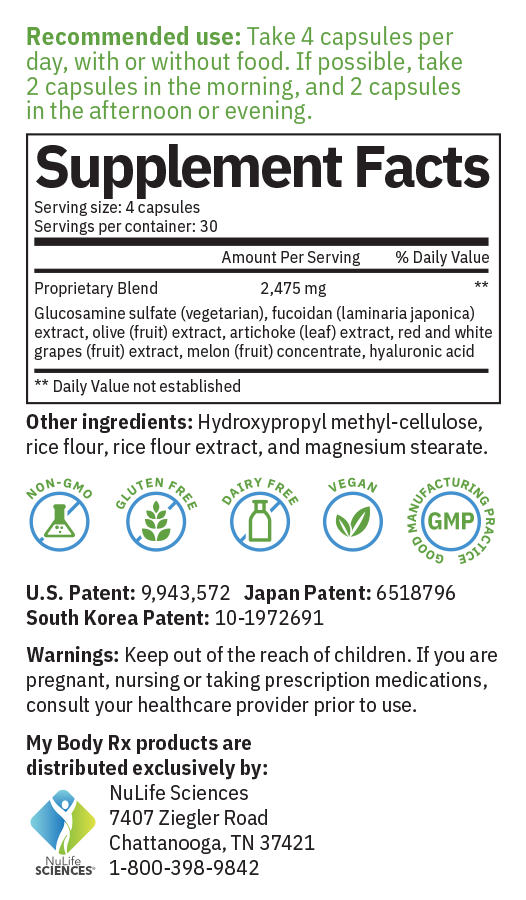

Patented Formulation with Three Classes of Compounds

Restorative Properties of Polysaccharides: Endocalyx is made with a brown seaweed called Laminaria Japonica. An extract is produced that is certified to have a minimum extract rate of 85% of the compound fucoidan sulfate. Fucoidan sulfate is validated as a hybrid of heparan sulfate and chondroitin sulfate and has a high binding affinity for heparanase. The fucoidan repairs the glycocalyx and prevents breakdown by inhibiting the heparanase activity. In addition to the fucoidan sulfate, Endocalyx also contains high molecular weight hyaluronan which is essential to provide the glycocalyx with its structural stability and dimension.

Regenerative Properties of Amino Sugars: A high dose of glucosamine sulfate, 1,500 mg (vegetarian) provides the building blocks for glycocalyx synthesis. Research confirms that glucosamine at this concentration boosts endothelial cell glycocalyx production.

Protective Properties of Antioxidants: Microvascular Health Solutions developed a next-generation proprietary blend of polyphenol and flavonoids consisting of the most efficacious fruits and vegetables clinically shown to produce anti-oxidant activity. Olive (fruit) extract, artichoke (leaf) extract, red and white grapes (fruit) extract. We increased the amounts of these ingredients to provide evidence based effective doses. We added superoxide dismutase (from bitter melon concentrate). We also added catalase (also from bitter melon concentrate). It is also verified that these antioxidant ingredients survive oral intake and arrive in the vascular compartment at clinically effective dosages.

Recommended dose: Four capsules twice daily, either two in the morning and two in the evening, or four all at one time. One bottle of 120 veggie capsules is a one-month supply.

Patents: Filed and Granted as a Method of Treatment for the Endothelial Glycocalyx based on the synergistic action of three classes of compounds. This patented anti-aging supplement formula has been clinically shown to improve the health of the glycocalyx using seven synergistic ingredients from three classes of compounds:

RESTORE: Polysaccharides – enables repair of glycocalyx matrix (fucoidan sulfate and HMW hylaronan)

REGENERATE: Amino sugars – precursor for polysaccharide biosynthesis (veggie glucosamine)

PROTECT: Antioxidants – protects endothelial polysaccharide from breakdown (polyphenol, flavonoids, SOD, catalase, heparanase inhibitor).

U.S. Patent Number: 9943572

Japan Patent Number: 6518796

South Korea Patent Number: 10-1972691